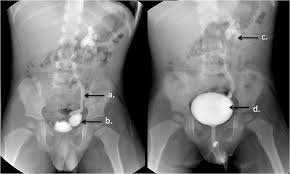

We provide quick and accurate Emergency Sonography, X-Ray, and Doppler services for immediate diagnosis.